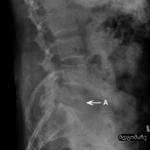

კომპრესიული მოტეხილობის რენტგენი: ლატერალური პროექციის რენტგენი L2 კომპრესიული მოტეხილობის დროს (A). შეინიშნება მალის სხეულის სოლისებრი დეფორმაცია

ექიმ Dr K. Singh საკუთრება; გამოყენებულია ნებართვით